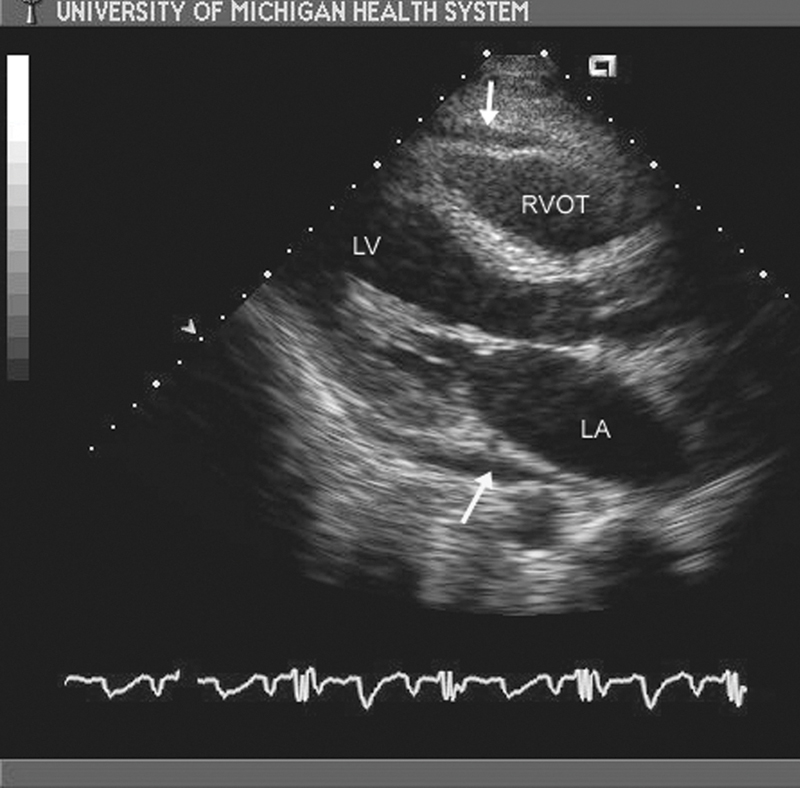

فحوصات تشخيصية لبعض امراض القلب والشرايين التاجية